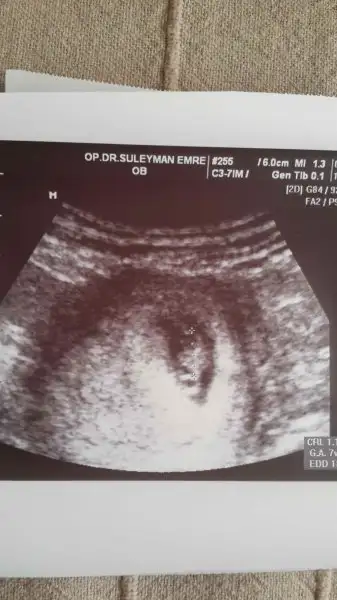

IMG-20160310-WA0009.webp buda 7+2 usg